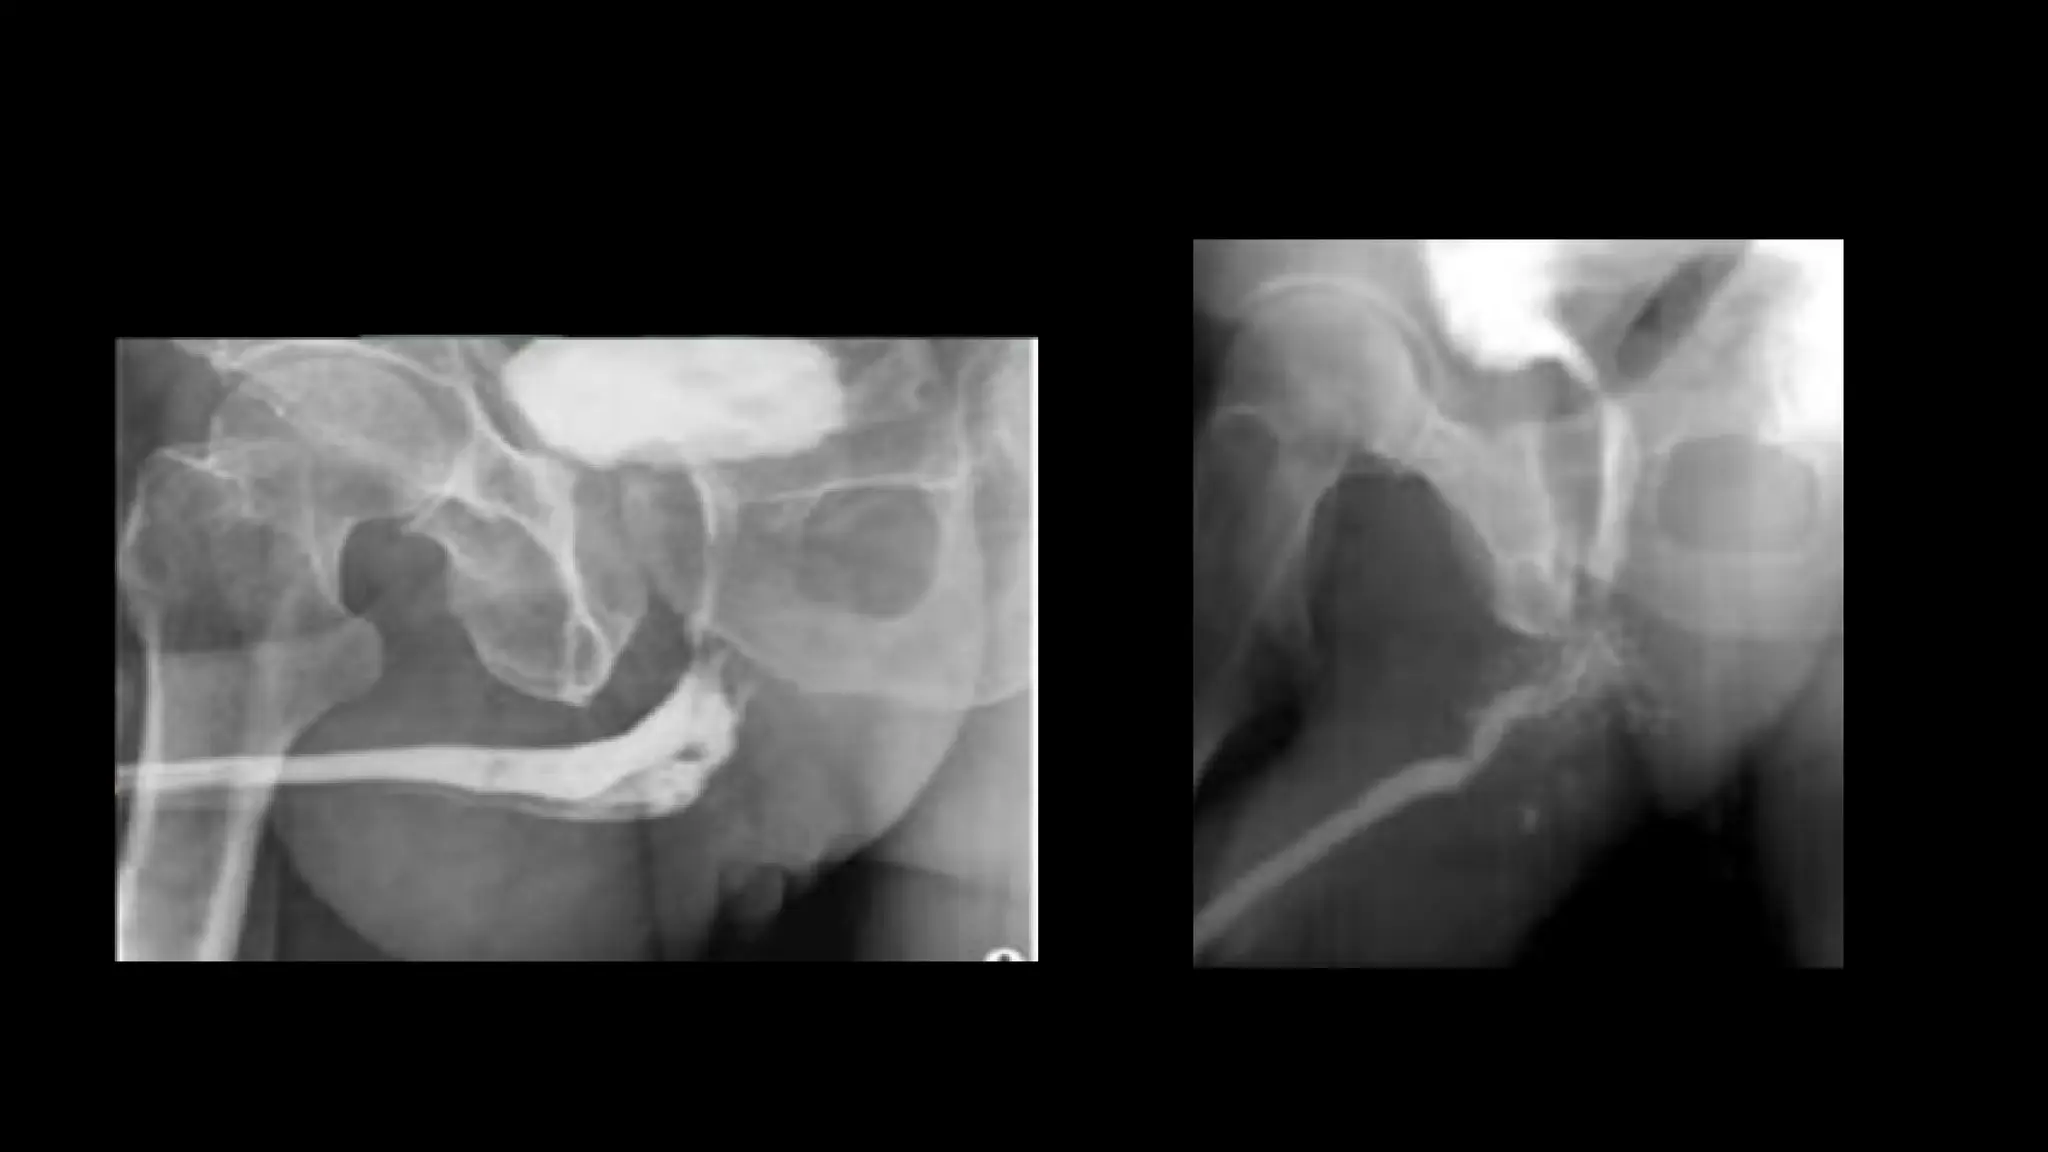

• MALIGNANT TUMORS:

• MC location-bulbomembranous

urethra.

• SCC-Irregular narrowing of

bulbar urethra with multiple

sinus tracts.

• MALIGNANT TUMORS: •MC location-bulbomembranous urethra. • SCC-Irregular narrowing of bulbar urethra with multiple sinus tracts.